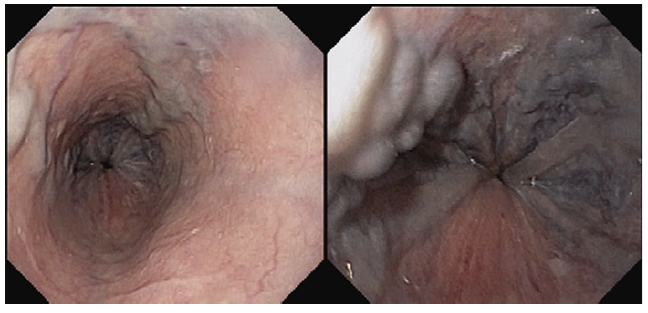

Endoscopy showed large proximal esophageal varices, without red spots, and mild portal hypertensive gastropathy (shown in Fig. 1). Abdominal ultrasound revealed slight hepatomegaly with irregular liver surface; no focal lesions; marked echogenicity of the fibrovascular axes and hilum; ectasia of the inferior vena cava (IVC) and hepatic veins; no portal vein abnormalities; mild splenomegaly (14 cm). A comprehensive chronic liver disease etiology panel was negative.

Coronary angiography ruled out coronary disease. Thoraco-abdominal computed tomography angiography showed enlarge-ment of the pulmonary artery with no evidence of thrombus, as well as absence of porto-systemic collateralizaion, portal vein thrombosis, and structural lung disease. A re-evaluation endos-copy showed large but reduced esophageal varices, without red spots (shown in Fig. 2).

Fig. 2. Large esophageal varices, reduced in size in comparison to the previous eval-uation, without red spots.